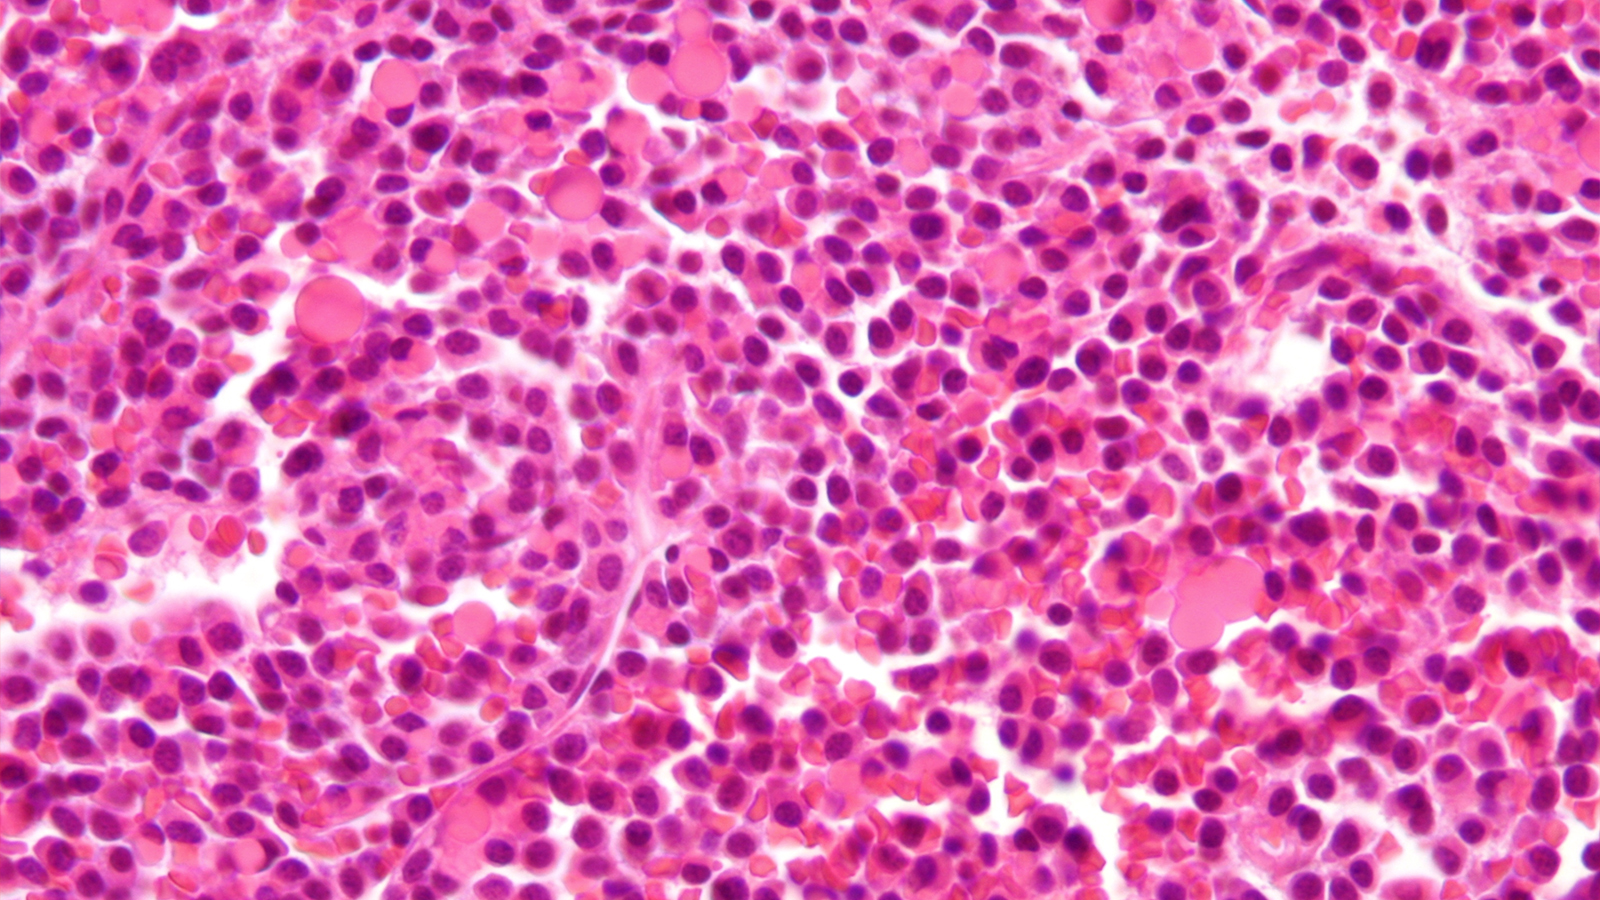

FDA approves first-of-its-kind blood cancer treatment

The FDA has approved Johnson & Johnson’s Tecvayli, a new blood cancer treatment for people with relapsed or refractory multiple myeloma.